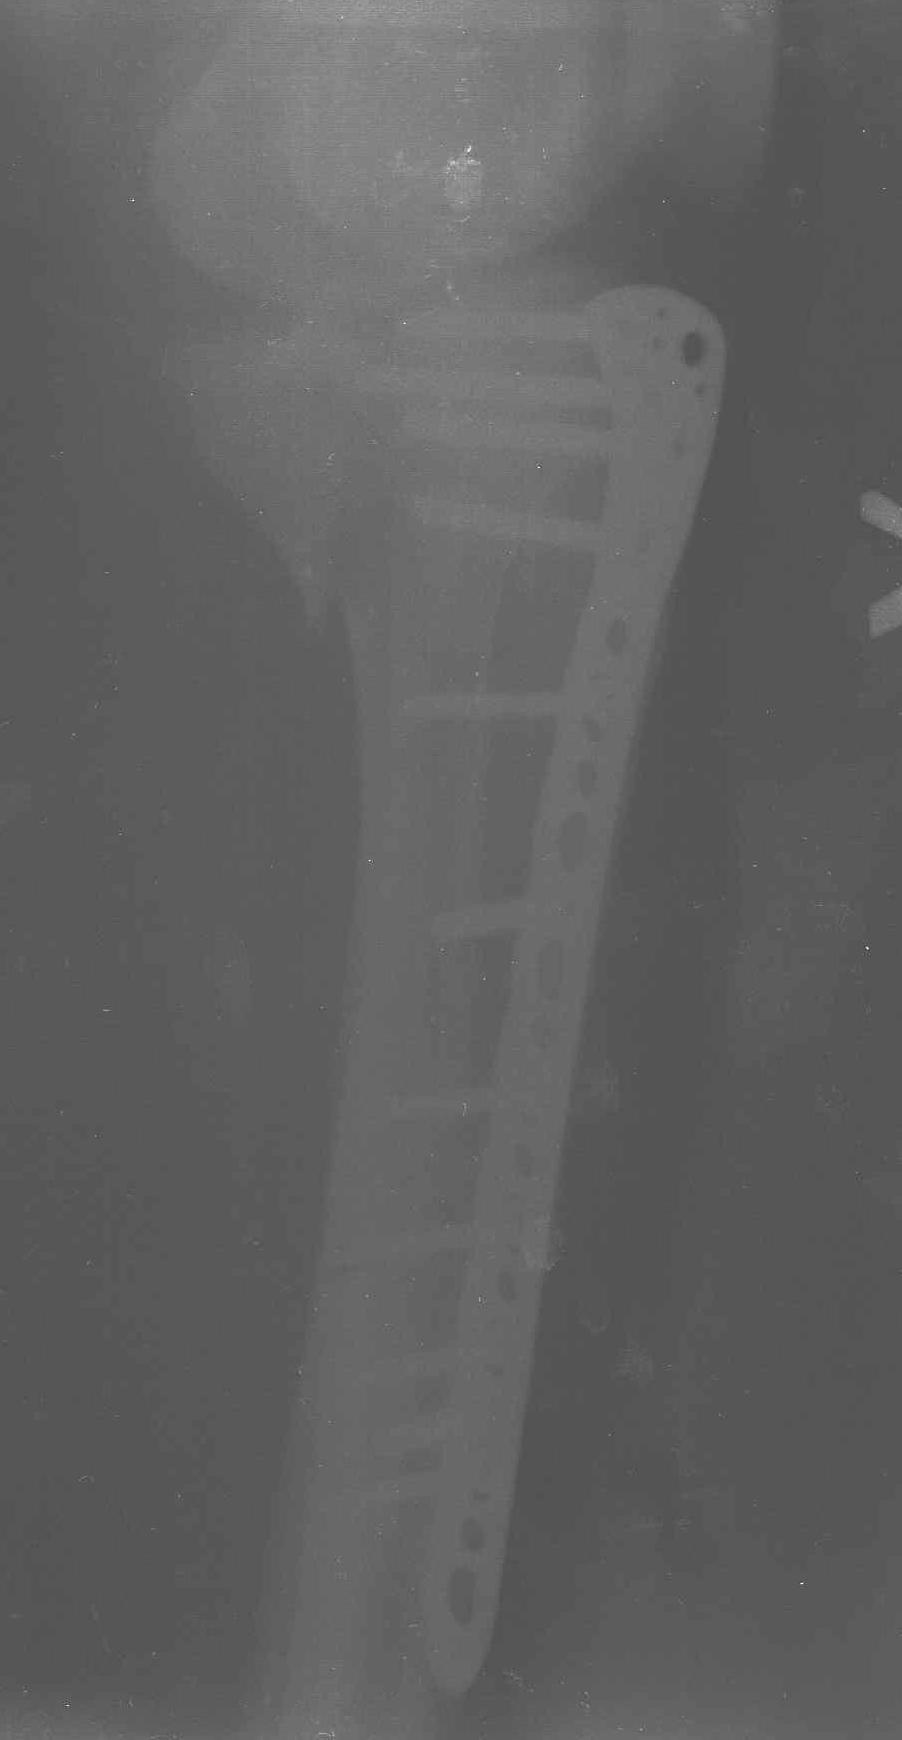

Уважаемые коллеги! В прошлую пятницу больной прооперирован - как и планировалось мыщелковая LCP от ChM. Малоинвазивно не получилось - один большой доступ :(. (но с минимальным скелетированием б/б кости).  Наружный мыщелок собрали, но по контролю видно, что задне-медиальный отдел метаэпифиза смещен. Фиксировать не стали (?). 4-е сутки после операции - по м/тканям без проблем. Дополнительная иммобилизация синтетическим тутором.

Интересно услышать ваши мнения, анализ ошибок...

P. S. перелом диафиза на контроле не совсем захвачен, но проблем там нет. Приношу извинения за низкое качество Р-грамм - выполнены на сканере (фотоаппарат не работает :)) .